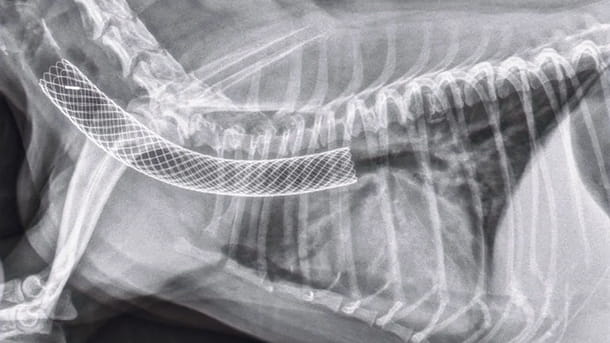

Tracheal stent

IR uses fluoroscopic image-guidance to perform minimally invasive procedures. These images are like roadmaps that permit the clinician to guide instruments such as catheters and guide wires through the body gain access to different body part for diagnostic and therapeutic reasons.